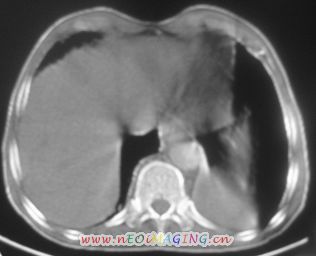

以下是引用卜一在2007-10-7 9:38:00的发言:[br]左下肺胸膜下团片影,内见含气支气管像,临近胸膜未见增厚。多考虑:1 左下肺炎症,建议消炎后复查!2 不除外肺隔离症合并感染!